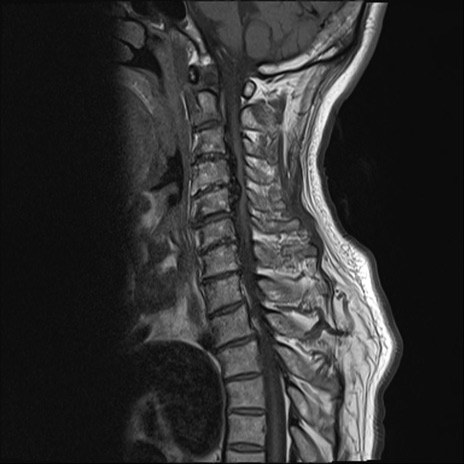

【整形】TIPS症例7 頚椎MRI T1WI(矢状断像)

頚椎MRI

T2WI(矢状断像)

矢状断像と横断像